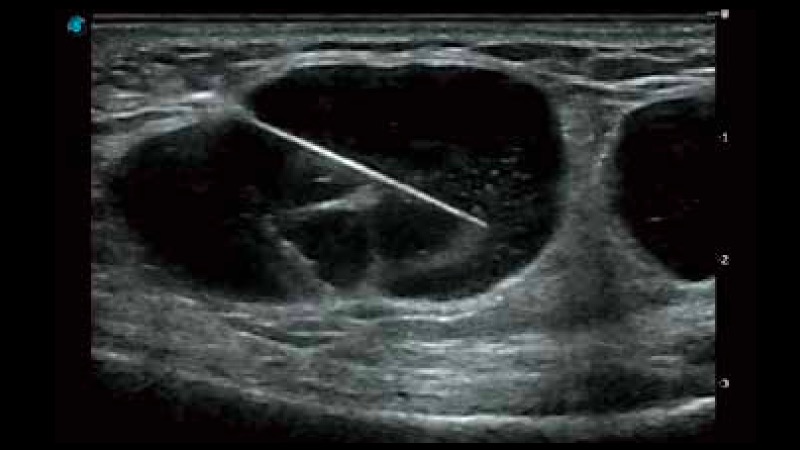

凭借开立医疗先进的成像技术和优异的探头技术提供的清晰的图像表现,您可以更自信地做出临床决策。